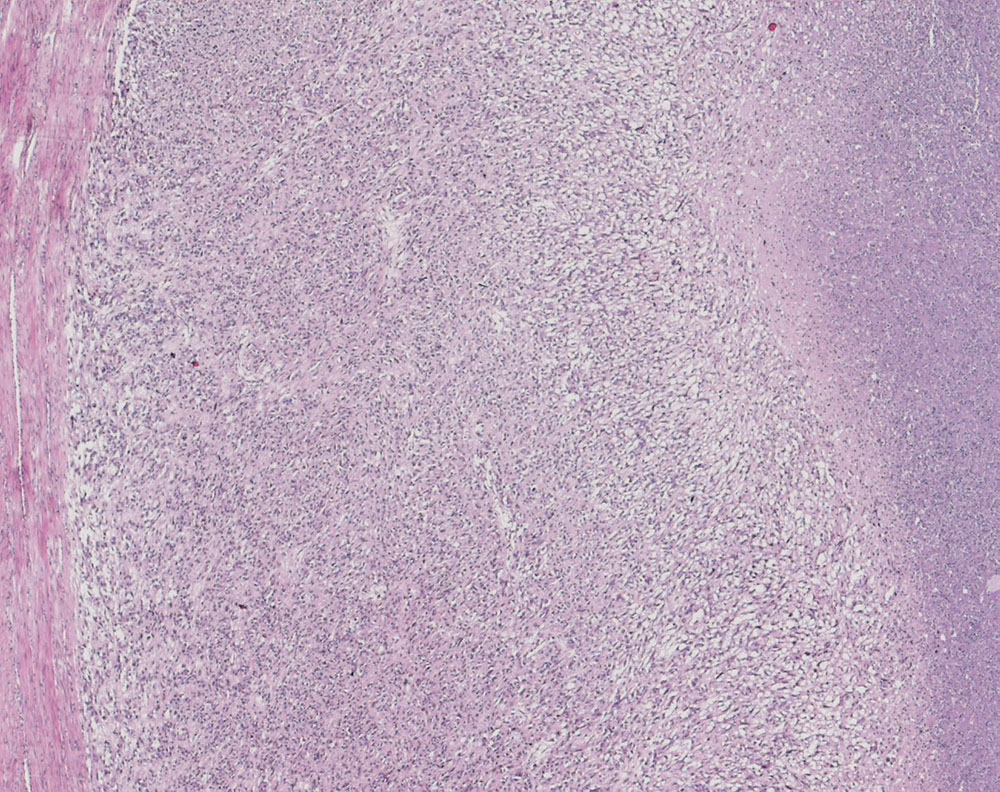

• Stellenweise unscharfe Begrenzung des Sarkoms zum nicht neoplastischen Myometrium (Fragment oben rechts).

• Tumornekrosen.

• Bereits in der Übersicht (10x) erkennbare diffuse signifikante Zellatypien.